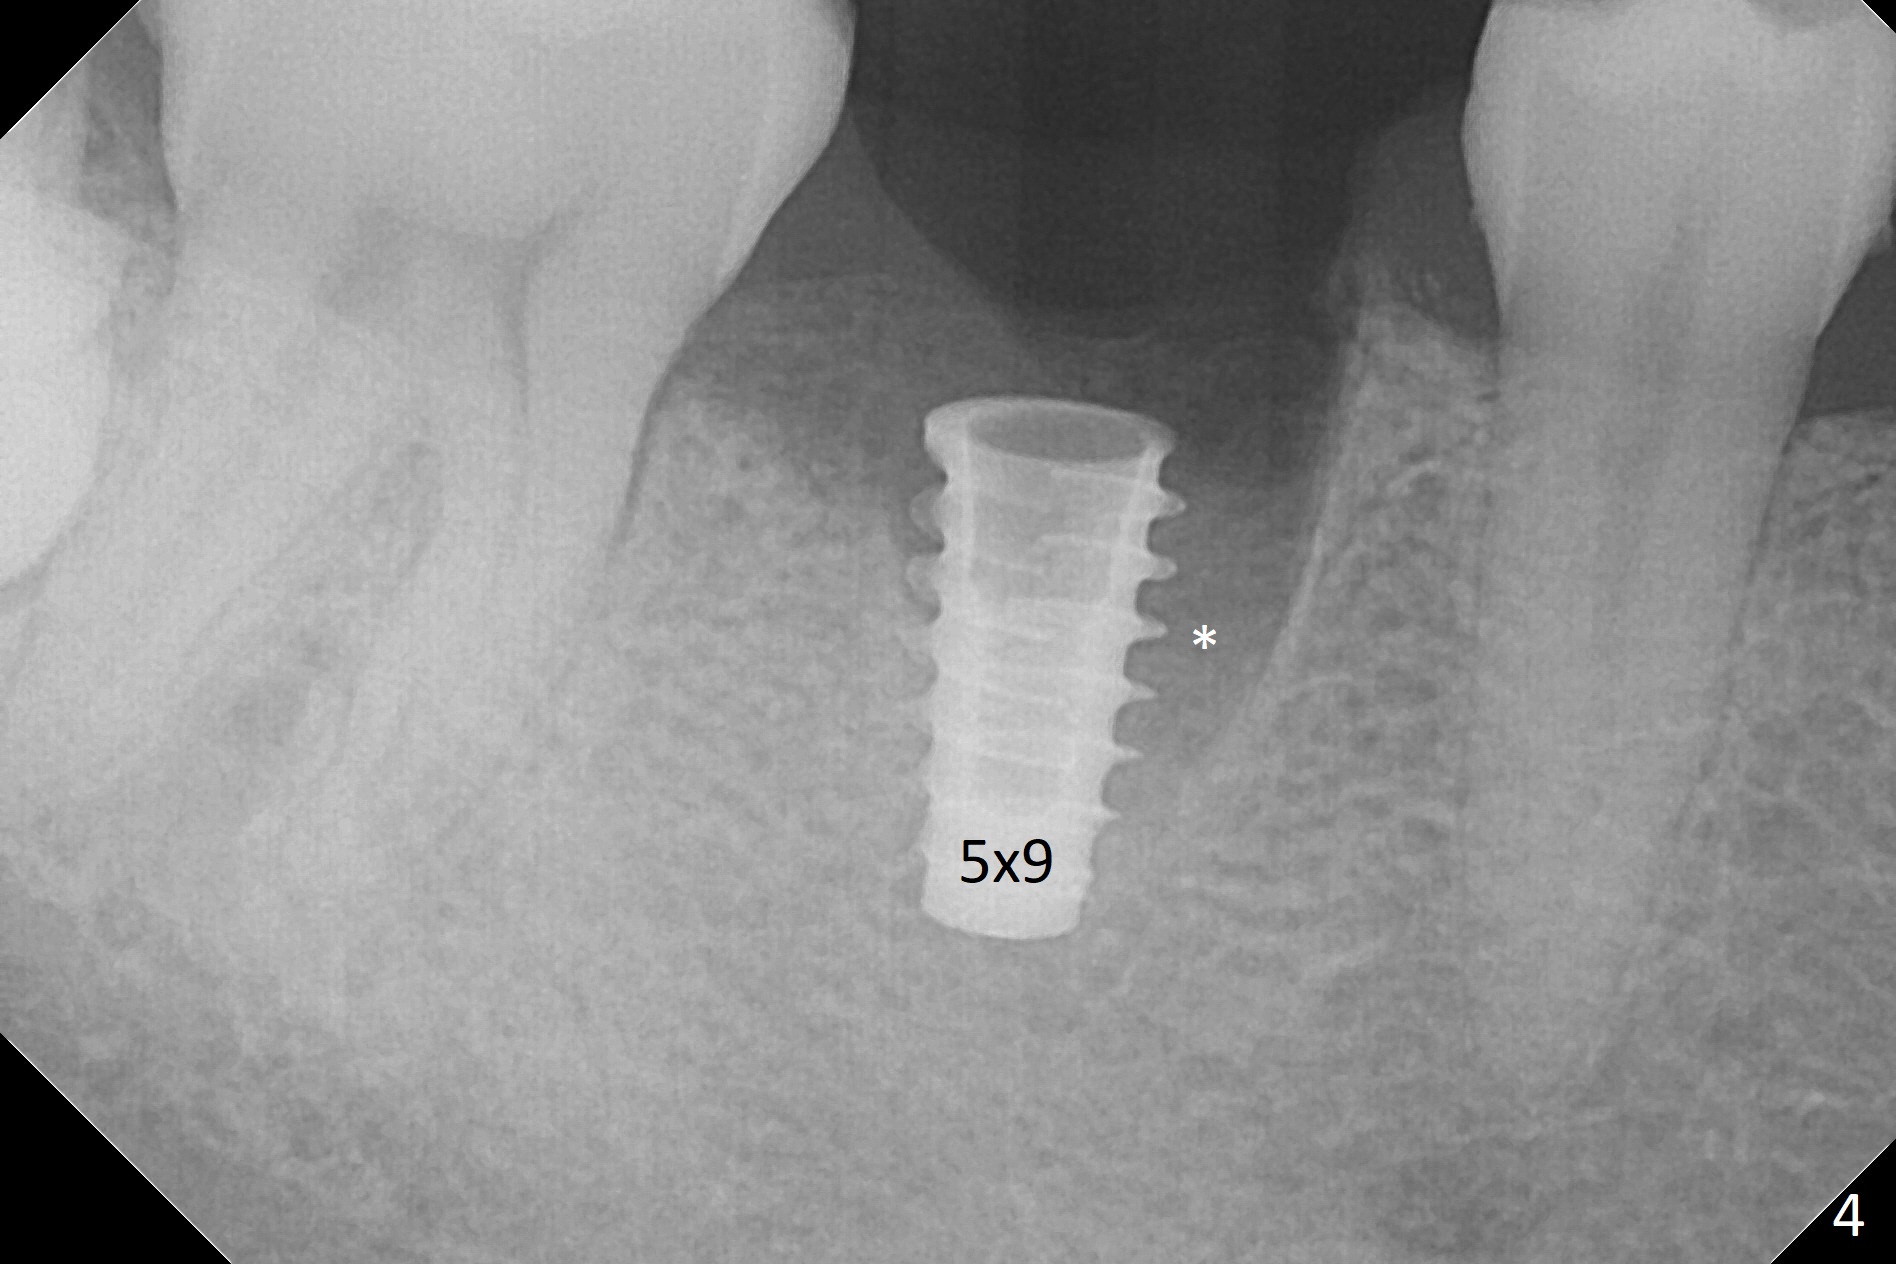

After removal of the residual roots at #30 (Fig.1), a thin septum (Fig.2 *) is removed with Rongeur (Fig.3). Following use of 4.8 mm Magic Drill, a 5x9 mm dummy implant is placed (Fig.4). To reduce socket gap (*), a 6 mm IBS implant is inserted with >50 Ncm (Fig.5). What is unexpected is heavy reduction in the height of a 6.5x4(3) mm abutment (A) because of the short crown height of the lower posterior teeth (Fig.1) and supraeruption of the tooth #3. The immediate provisional is unstable postop. The remade one dislodges soon, so does the abutment (Fig.6, 3 months postop). It appears that bone pattern in the distal socket changes.